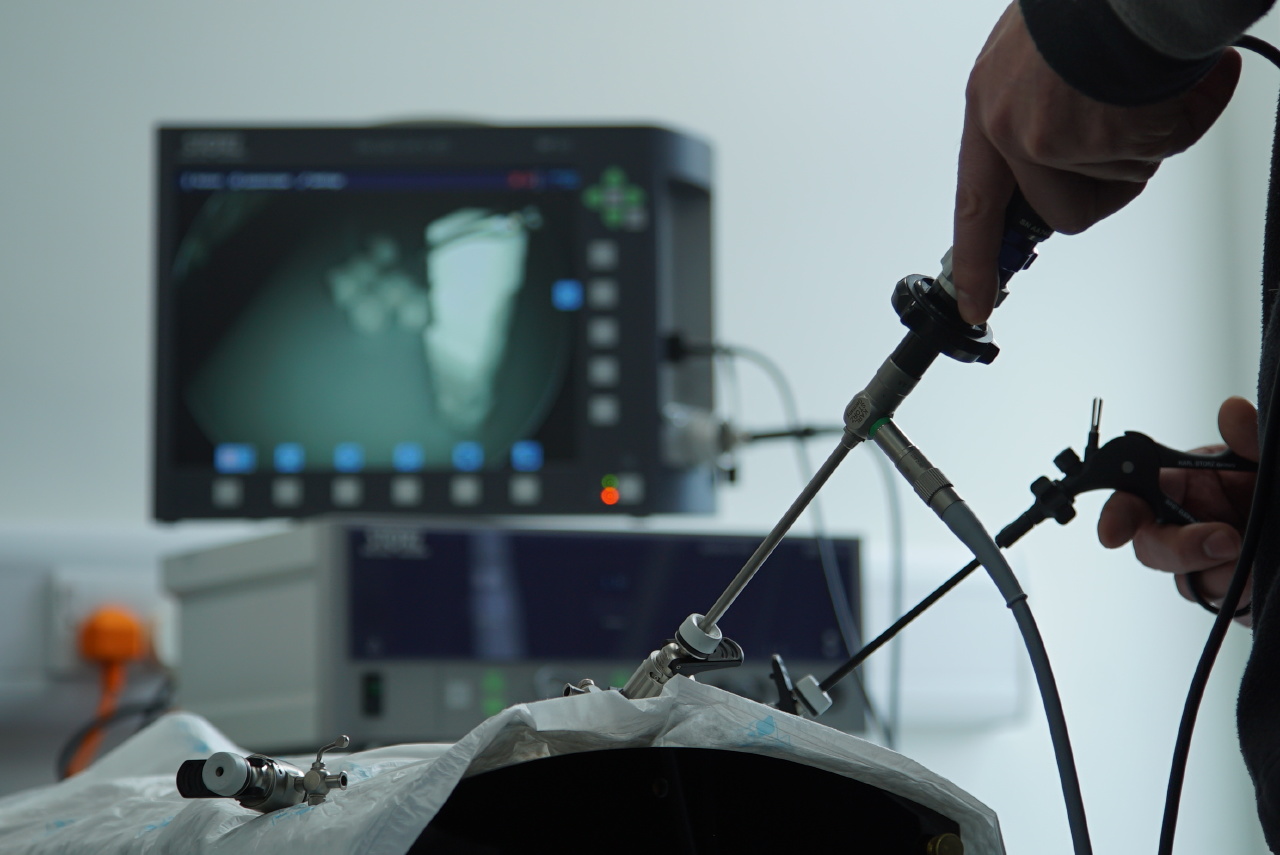

This two-day course aims to give you hands-on with less commonly performed abdominal procedures and also give an introduction to thoracic surgery. While lecture sessions will cover indications and post-operative management, the main focus will be based on performing the surgeries themselves.

Highly practical cadaver-based sessions across both days will provide hands-on experience, with discussion of tips and techniques to optimise outcomes.